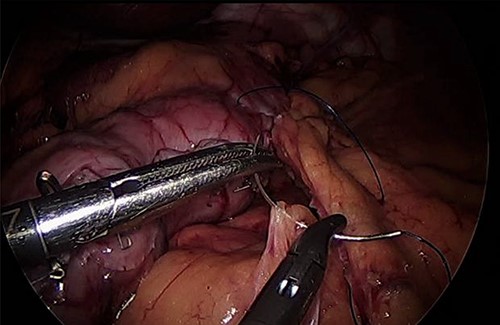

For LLA, ports were inserted similar to our preferences for LSG, which are 5 mm at left upper quadrant, 12 mm at superior and to the right of umbilicus, 5 mm port at right upper quadrant and a Nathanson liver retractor at epigastric area. In Patient 3 with left adrenal mass, we proceeded with LSG first since the patient is not a high risk and that LSG will ease the LLA from exposure standpoint. The greater omentum was divided till the gastroesophageal junction, followed by applying 60 mm black Ethicon Tristapler at the antrum followed by purple staplers along a 36Fr bougie. It is our preference to apply clips long the sleeve but not a full deployment to control bleeding. Using the supragastric approach described before, the left adrenal gland was reached easily using the left diaphragmatic crus as a landmark and tracing the left phrenic vein to reach the left adrenal vein [7]. Using energy device, the left adrenal vein was controlled and attachments were released liberating the left adrenal gland and placed in the endobag. After assuring hemostasis, we completed the procedure by plicating the stomach at the upper half of the sleeve and omentopexy of the whole sleeve till the end of the divided omentum (Fig. 4).

As for the LRA, ports are inserted in similar fashion as the LLA but with more to the right side. An additional port at the right midclavicular line is an optional (Fig. 5). In Patient 1, we started with the LLA to control the blood pressure caused by the adrenal gland and to prevent unnecessary bleeding from occurring. Conversely, we started with LSG in Patient 2 because the priority was controlling his comorbidities by weight reduction. The right hepatic lobe was retracted to expose the subhepatic area. The right hepatic ligaments were released, exposing the inferior vena cava. Dissection lateral to the IVC was continued exposing the right adrenal (Fig. 6). Complete dissection of the adrenal gland was completed and the pedicle was controlled using energy device (Fig. 7). There was constant communication with the anesthesia team during the surgery. After complete dissection of the adrenal gland, it was placed in the endobag and the LSG was conducted similar to the above-mentioned steps (Fig. 8).